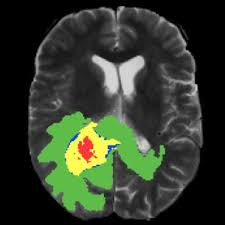

Brain Cancer Causes Types Symptoms Treatment Stages Survival Rate from images.medicinenet.com People exposed to very high doses of radiation to the head. There is no definitive cause of brain tumors or brain cancer, though certain factors may increase the risk. In the past two decades brain tumor rates have risen in several industrialized countries, including the united states. As the tumor grows, it creates pressure on and changes the function of surrounding brain tissue, which causes signs and symptoms such as headaches, nausea and balance problems. The incidence increased by 35 percent in children younger than 15, according to the website pediatric oncology education materials, which provides information for healthcare professionals. A brain tumor is a mass or growth of abnormal cells in your brain. A brain tumor can form in the brain cells (as shown), or it can begin elsewhere and spread to the brain. Some brain and spinal cord tumours are more common in people with certain inherited or genetic conditions.

There is no definitive cause of brain tumors or brain cancer, though certain factors may increase the risk. Glioblastomas (the type of brain cancer linked to cell phone radiation) and central nervous system tumors are increasing in young americans, in precisely the areas of the brain that absorb most of the microwave radiation emitted or received by phones. An estimated 4,630 new cases of pediatric brain tumors will be diagnosed in the u.s. A primary malignant brain tumor is a rare type of cancer accounting for only about 1.4% of all new cancer cases in the u.s.the most common brain tumors are known as secondary tumors, meaning they have metastasized, or spread, to the brain from other parts of the body such as the lungs, breasts, colon or prostate. This can be caused by growth of the tumor itself, swelling in. However, some specific types of brain tumors, such as meningioma, are more common in women. These brain tumors are usually benign. A brain tumor, known as an intracranial tumor, is an abnormal mass of tissue in which cells grow and multiply uncontrollably, seemingly unchecked by the mechanisms that control normal cells. Bigger brains have more brain cells, and thus a greater potential for cell mutations that lead to cancer. A brain tumor can form in the brain cells (as shown), or it can begin elsewhere and spread to the brain. Cancers that begin in the brain do not appear to be increasing. In general, men are more likely than women to develop a brain tumor. Recently, an increasing incidence of brain tumors has been reported from multiple studies.